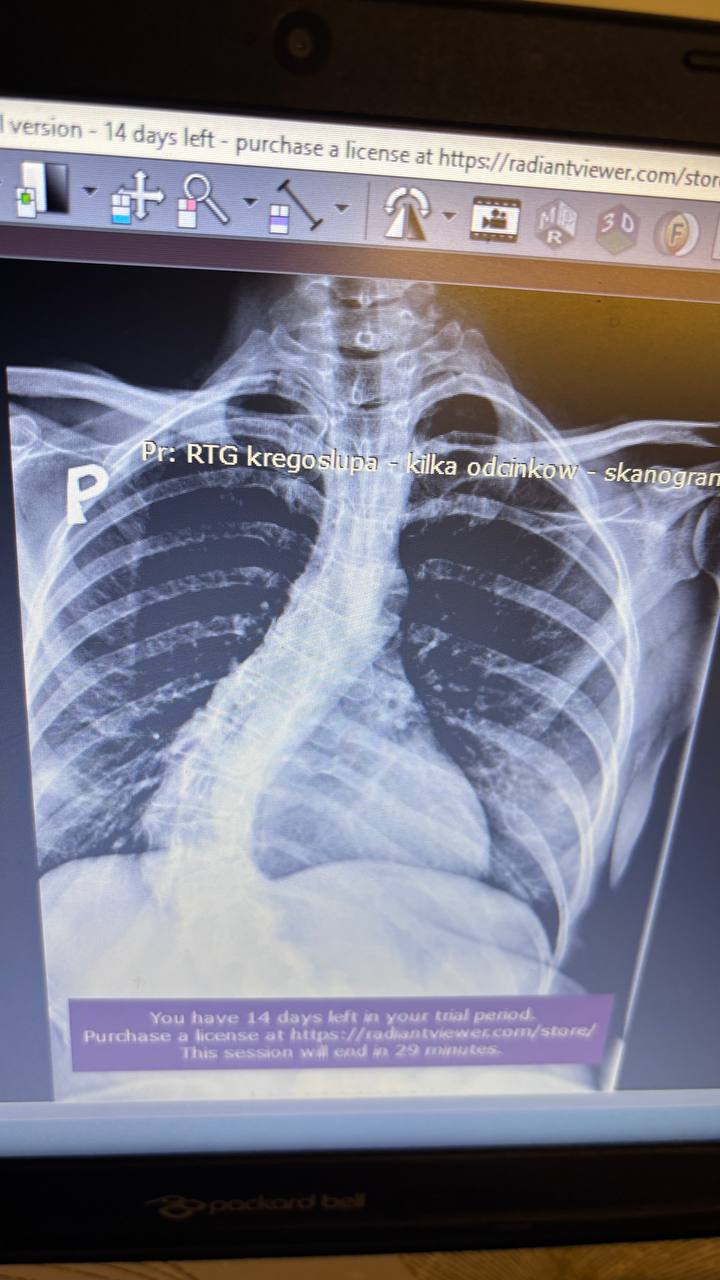

Діагноз: Ідіопатична сколіотична деформація хребта в дорослому віці. Правобічний реберний горб.

Сколіотична деформація хребта — це не лише викривлення спини.

У дорослому віці тяжкий сколіоз часто продовжує прогресувати на 1–3° щороку, поступово руйнуючи хребет.

Лікарі рекомендують складну операцію:

Корекція сколіотичної деформації (категорія 4)